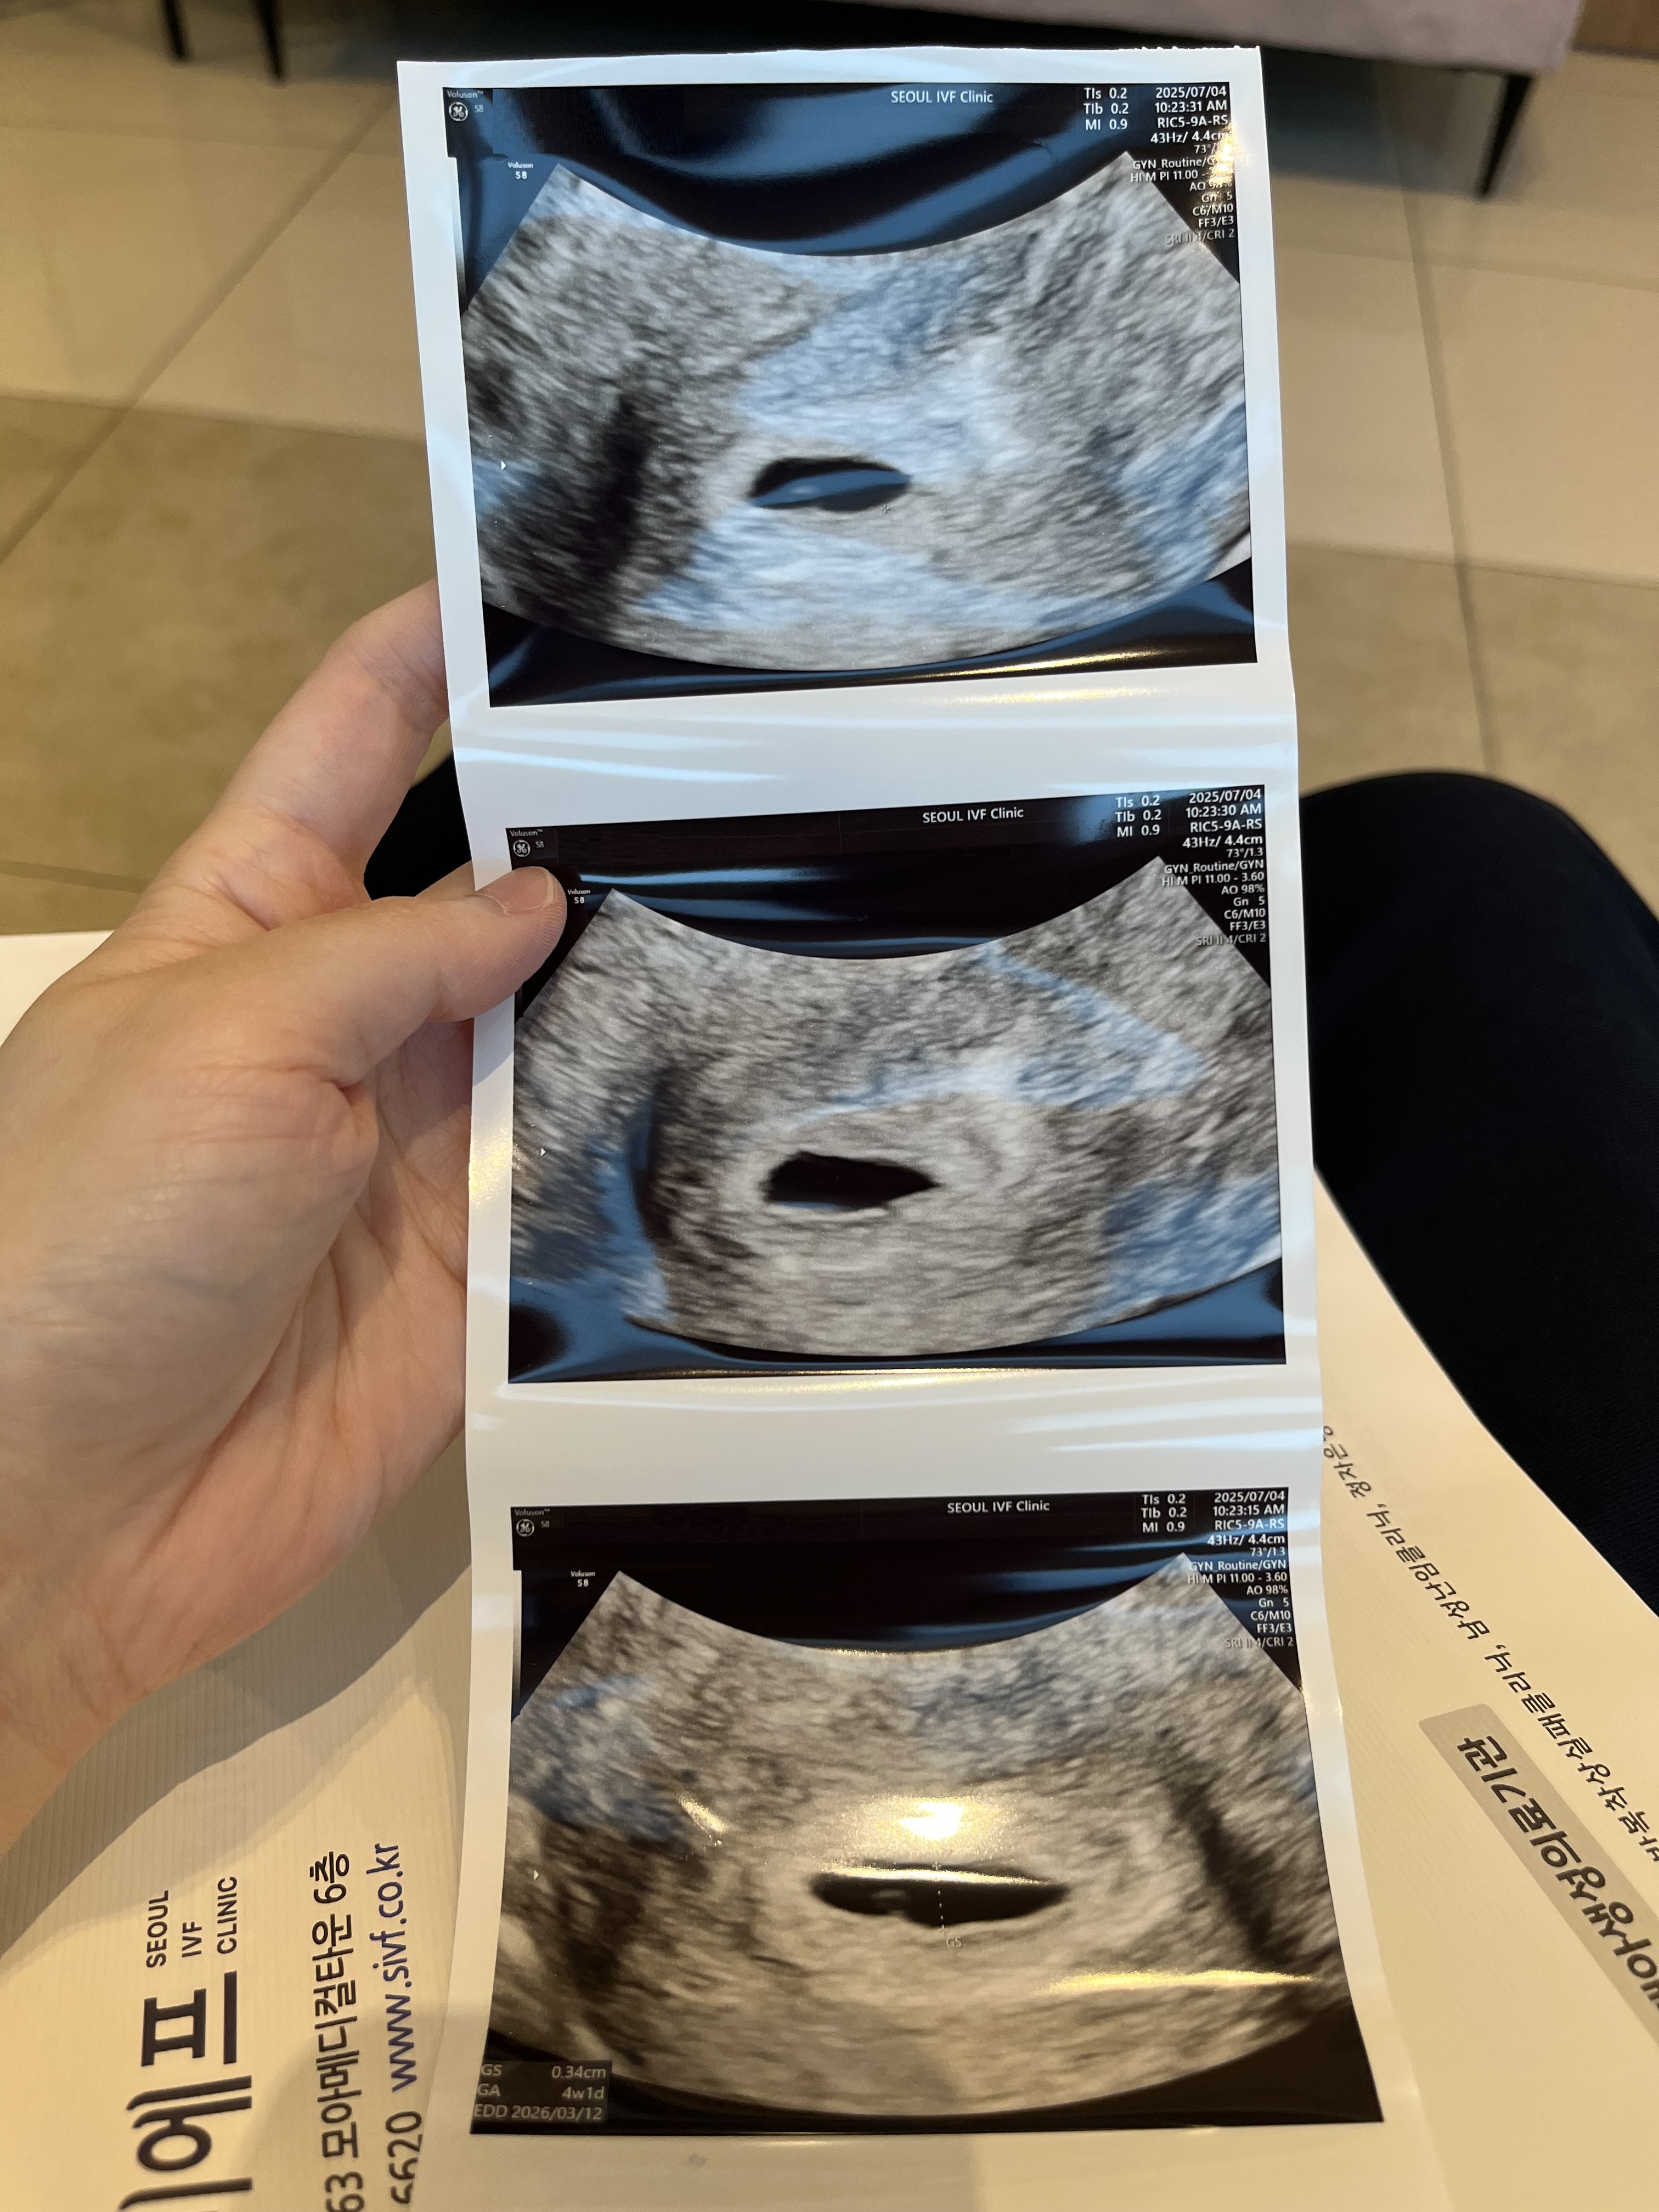

| 치료 도중 느꼈던 가장 기뻤던 순간과 절망적인 것들은 무엇인가요? 잊지 못할 경험이 있나요? | 가장 기뻤던 순간은 아기집을 초음파로 확인하고, 첫 임신확인서를 받았을 때였습니다. 화학적 유산 경험이 있었던 만큼, 피검사 수치보다는 아기집을 직접 보고 싶다는 간절한 마음이 컸습니다. 그 소망이 이루어졌을 때의 기쁨은 말로 표현하기 어려웠습니다. 가장 절망적이었던 순간은 다낭성난소증후군으로 인해 난자 채취 27개 중 5일 배양 후 살아남은 배아가 3개뿐이었을 때였습니다. 또 사전에 PGT 검사를 요청했는데 최종적으로 통과된 배아가 1개라는 소식을 들었을 때는 마음이 무너져 내렸습니다. 하지만 결국 그 1개의 배아가 저희에게 기적을 가져다주었습니다. |